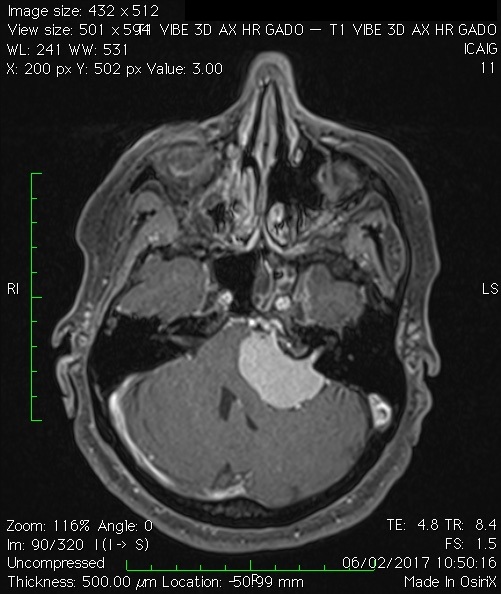

Les méningiomes

Ces tumeurs se développent à partir des méninges, les membranes qui entourent le cerveau et la colonne vertébrale. Ces tumeurs sont généralement bénignes. Les symptômes varient selon l’endroit où se trouve la tumeur et de sa taille (oreille, nez). Il peut affecter la vision et l’ouïe ou causer des problèmes de mémoire.

Le traitement d’un méningiome comprend la surveillance radiologique de la tumeur, une intervention chirurgicale souvent en association avec l’équipe de neurochirurgie pour son exérèse, ou la radiochirurgie stéréotaxique. Si la tumeur est à l’origine de symptômes, tels que des vertiges ou une perte auditive, ou s’il grandi lors du suivi radiologique, une exérèse est réalisée.

Certains patients ont également besoin de radiochirurgie comme traitement primaire ou d’appoint.